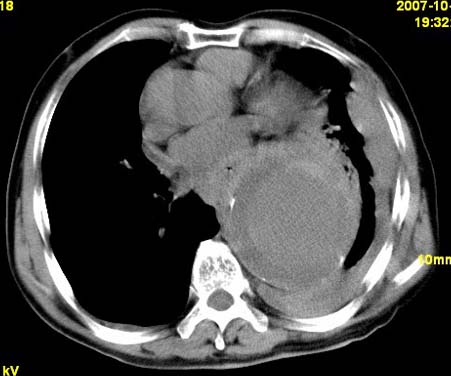

标题: CT10190:男,70,胸部疼痛数年,加重一天。典型病例。 [打印本页]

标题: CT10190:男,70,胸部疼痛数年,加重一天。典型病例。

典型降主动脉瘤伴血栓形成.瘤体下部局部边缘不清,结合病史,不除外局部撕裂外渗可能.另左侧胸水,肺部压迫不张改变.建议增强进一步检查.

典型降主动脉瘤伴血栓形成。支持:降主动脉瘤!

考虑胸主动脉瘤并血栓形成,胸腔积液

1.降主动脉瘤伴血栓形成.2.左侧胸腔积液,考虑为主动脉瘤破裂所致。

降主动脉明显增粗,边缘模糊,周围低密度影,双侧胸膜腔少量积液,结合临床考虑胸主动脉瘤破裂并双侧胸腔积液。